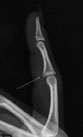

Choosing the right hand Therapist starts with them being able to read your X-rays and then fabricate the right brace for you. The therapists at Action Rehab are experienced in assessing and reading X-rays.

Our therapists do regular GP and Emergency Doctor training and can advise on the most appropriate action for your Fractured Finger treatment.